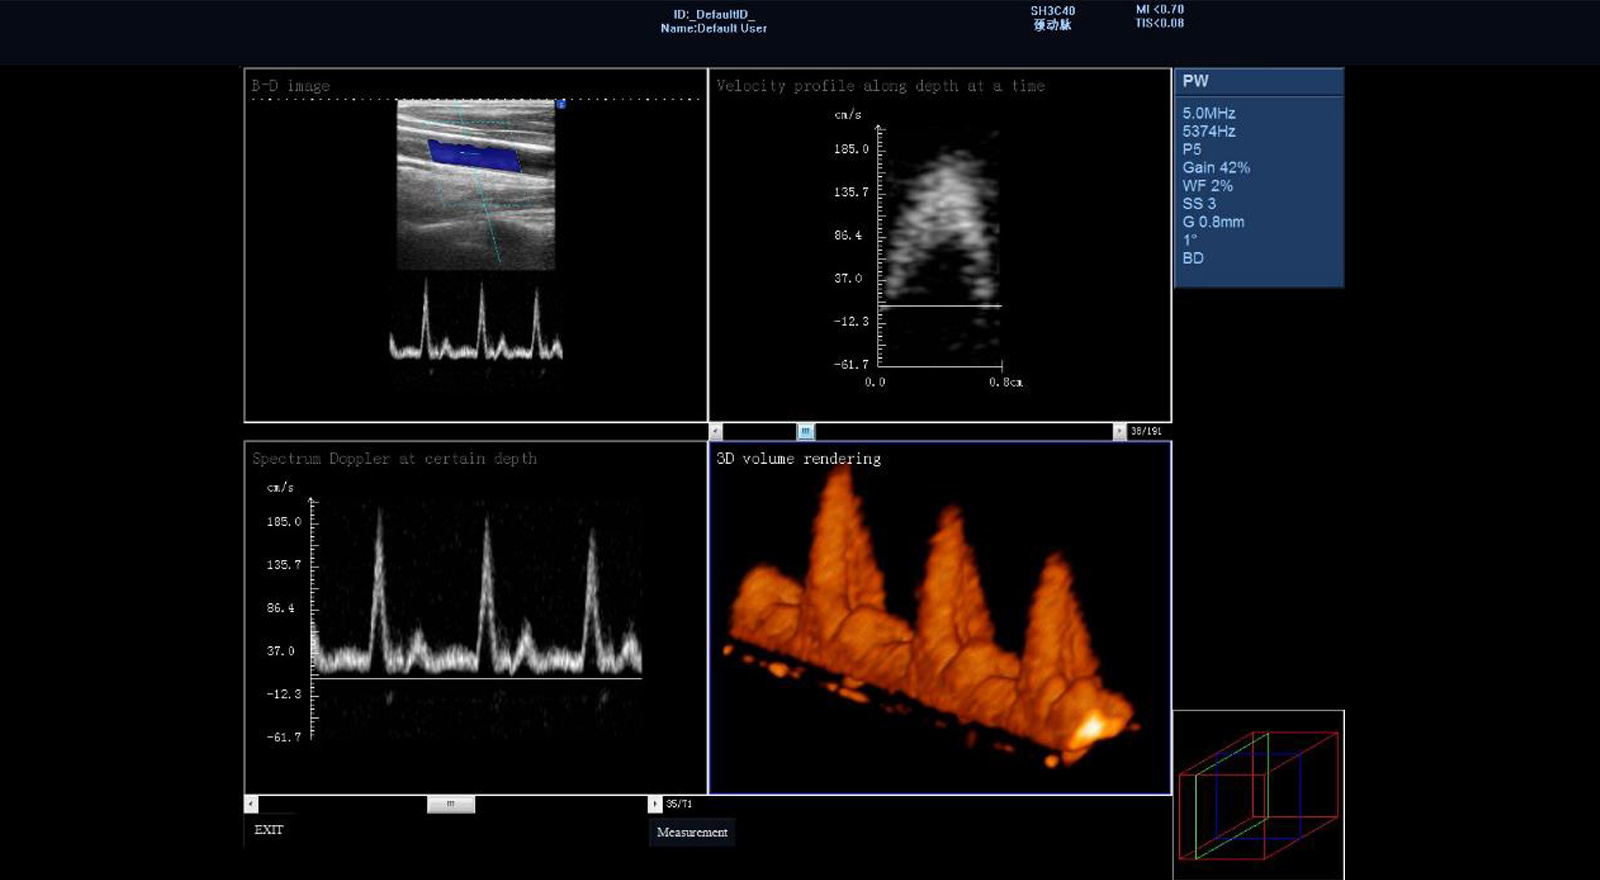

三维频谱成像

使用多采样门技术来估算一段时间之内流过血管的血流流量。可以帮助临床准确测量血流速度信息、评估血管硬化情况及精准血流量